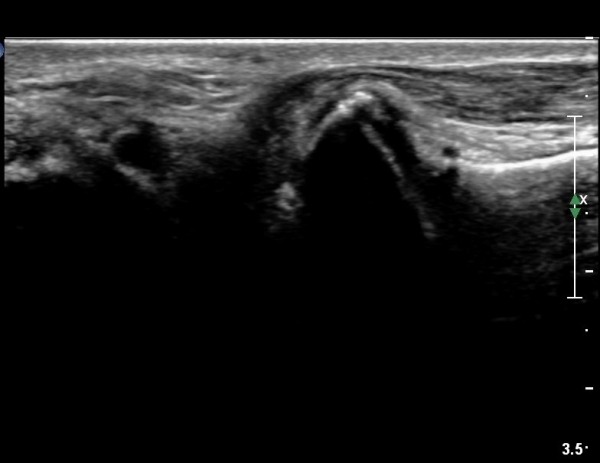

Á¾°ñ Àü¹æ µ¹±â(anterior process) °ñ±Ø°ú Ȱ¾×¸·¿° ¼Ò°ßÀ» º¸ÀÓ(»çÁø 3, 4).